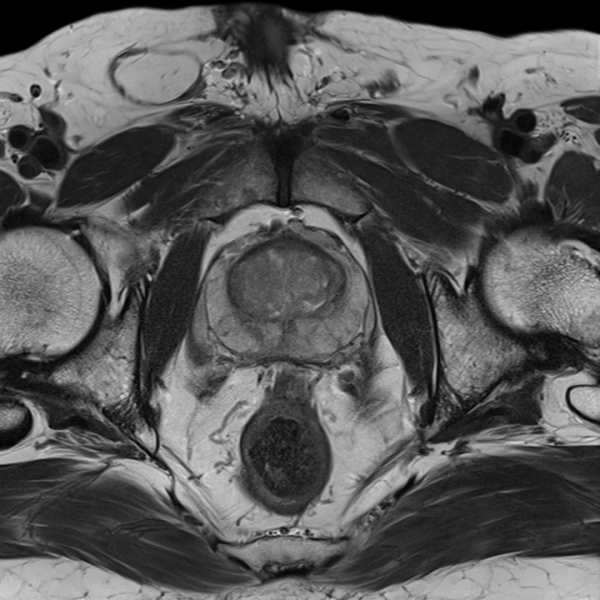

Одним из распространенных заболеваний среди мужчин является патология предстательной железы. Только МРТ простаты с контрастированием может указать на наличие болезни. Благодаря полученному результату врач сможет назначить правильное и комплексное лечение.

Компьютерная диагностика лучше, нежели старые способы исследования. При онкологии предстательной железы измененная ткань хорошо визуализируется. Опухоль можно рассмотреть тогда, когда стандартные методы ее не отображают.

Простата обладает маленькими размерами и располагается в организме достаточно удаленно, поэтому, при диагностировании, могут использоваться разные виды исследования. Мультипараметрическая МРТ простаты в этом плане предоставляет максимум возможностей.

Данная диагностика включает в себя все известные способы проведения МРТ. Эффективность данного исследования невероятно высока. Врач благодаря этому виду диагностирования получит не только данные о наличии раковой опухоли, но и сможет точно определить степень развития, а также то, какие ткани повреждены.